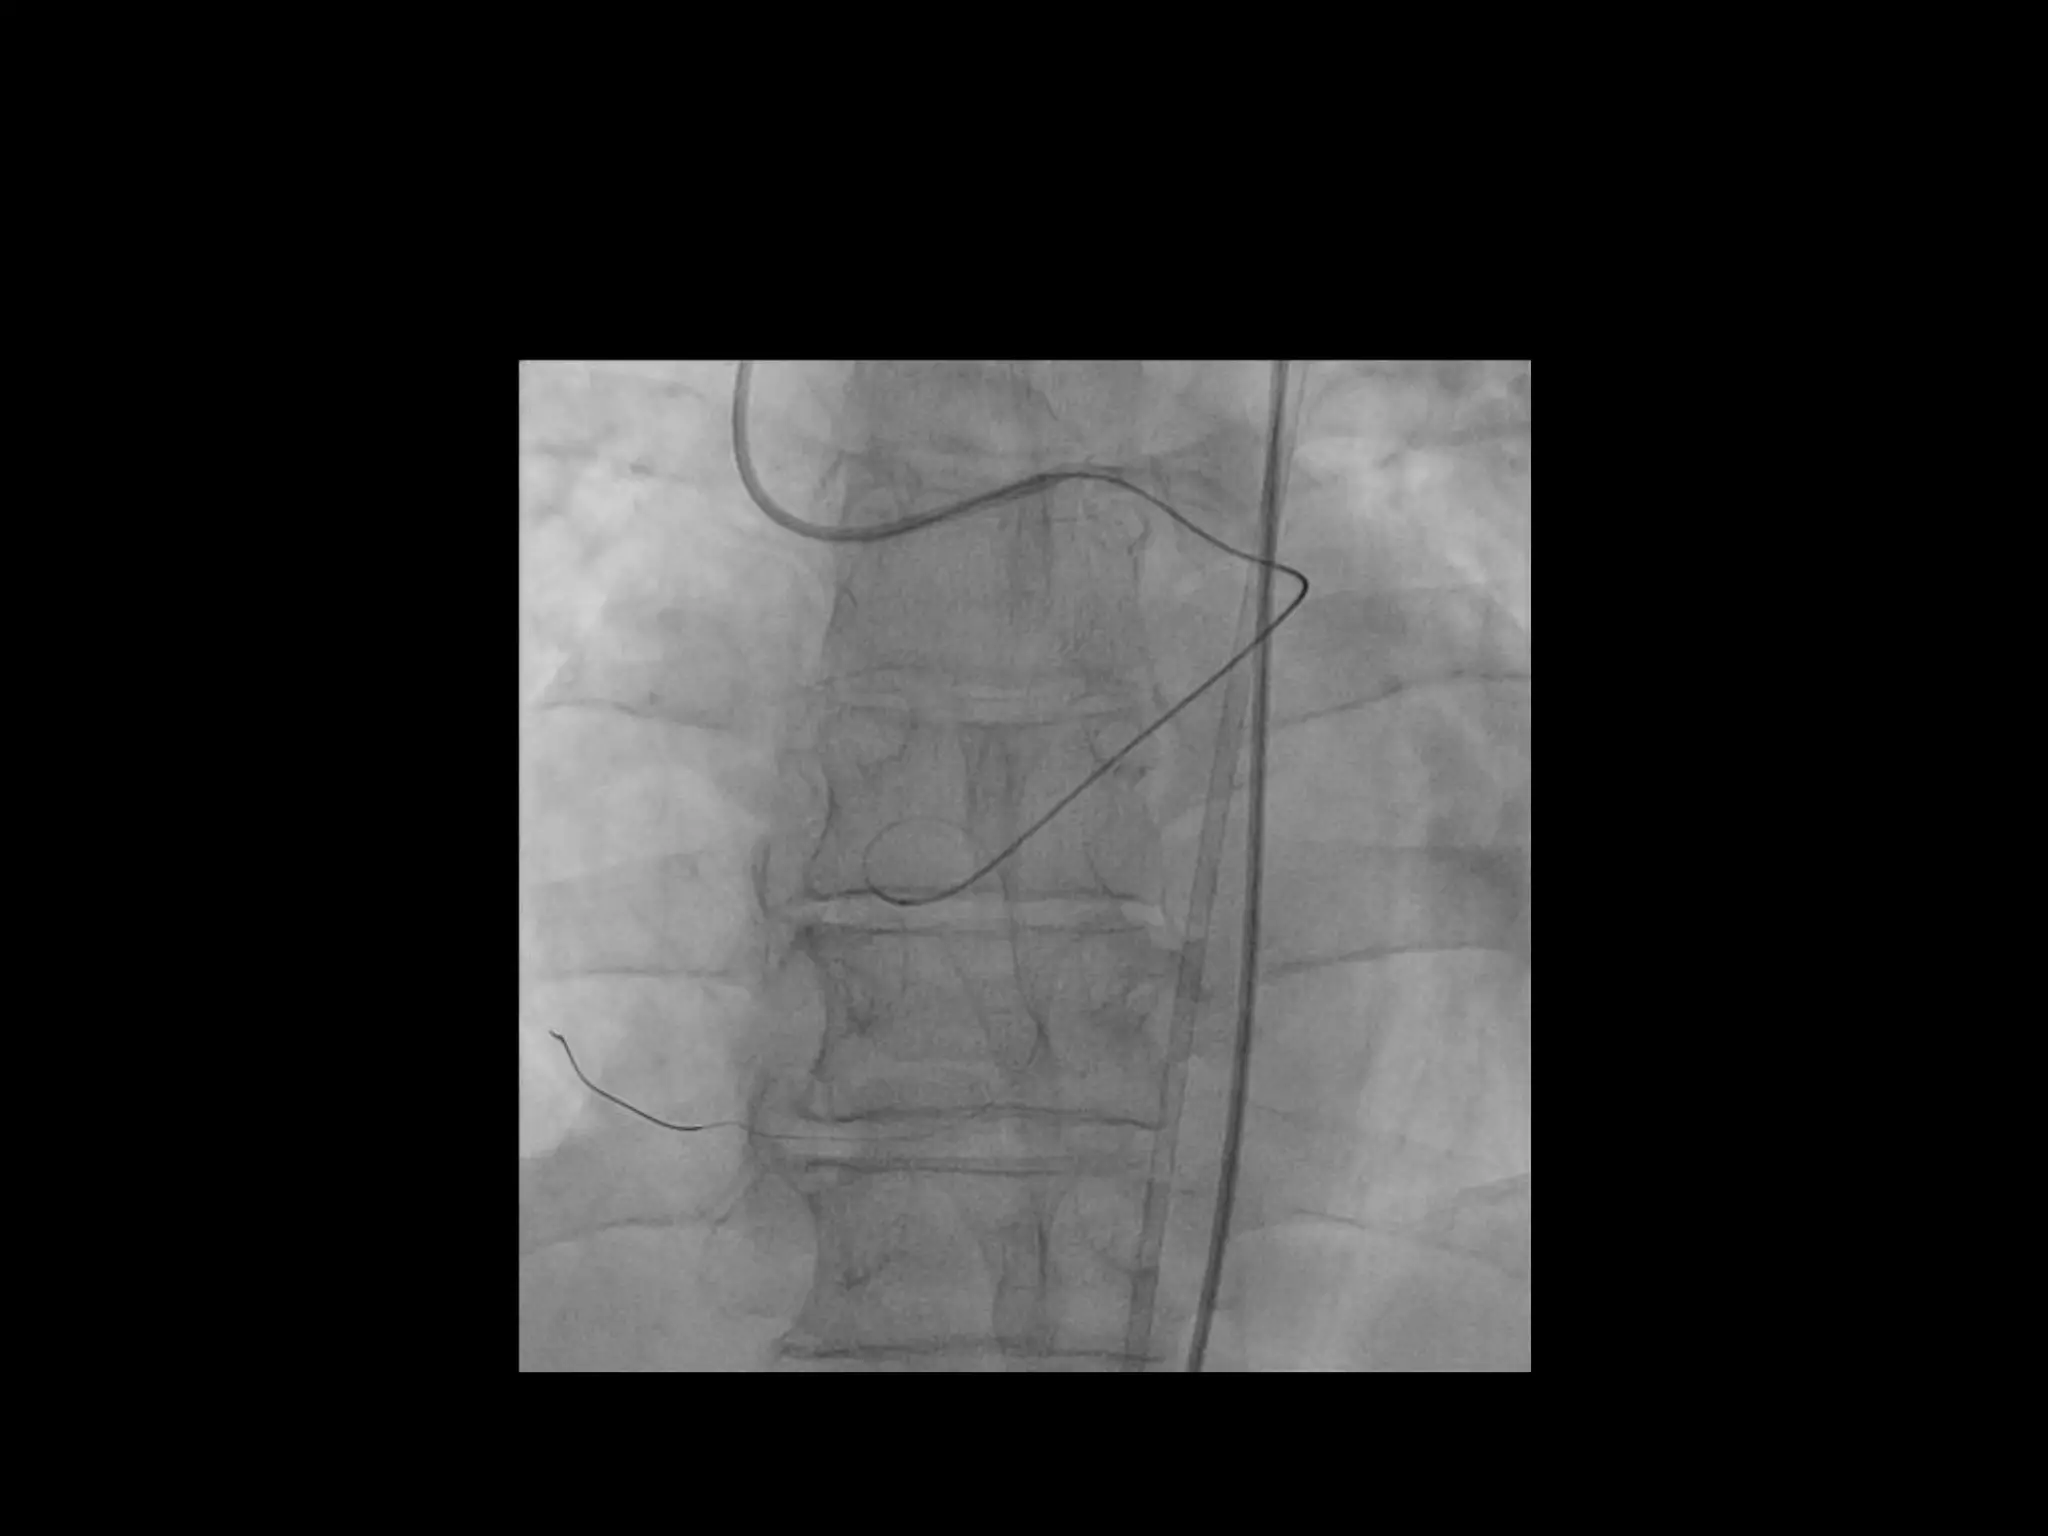

This document provides guidance on evaluating the feasibility of percutaneous coronary intervention (PCI) for a chronic total occlusion (CTO). Key factors to consider include: the patient's tolerance for a long procedure, contrast load, and radiation exposure; the CTO's proximal cap ambiguity, length, distal landing zone, and presence of interventional collaterals; and ensuring good quality angiography. With adequate planning and use of appropriate CTO techniques, feasibility is nearly always present for symptomatic patients. Success rates of CTO-PCI are reported to be 94% when using a planned approach.